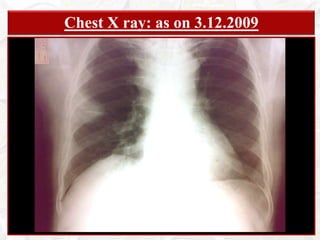

PATIENT  PARTICULARSKHAGEN BARUAH68 years; Male; HinduRetired Clerk from Assam State Electricity BoardAddress: Doom Dooma, Dist: Tinsukia, AssamBed: 88; Unit: Male Med Unit VDate of Admission: December 5th, 2008Date of Examination: December 14th, 2008